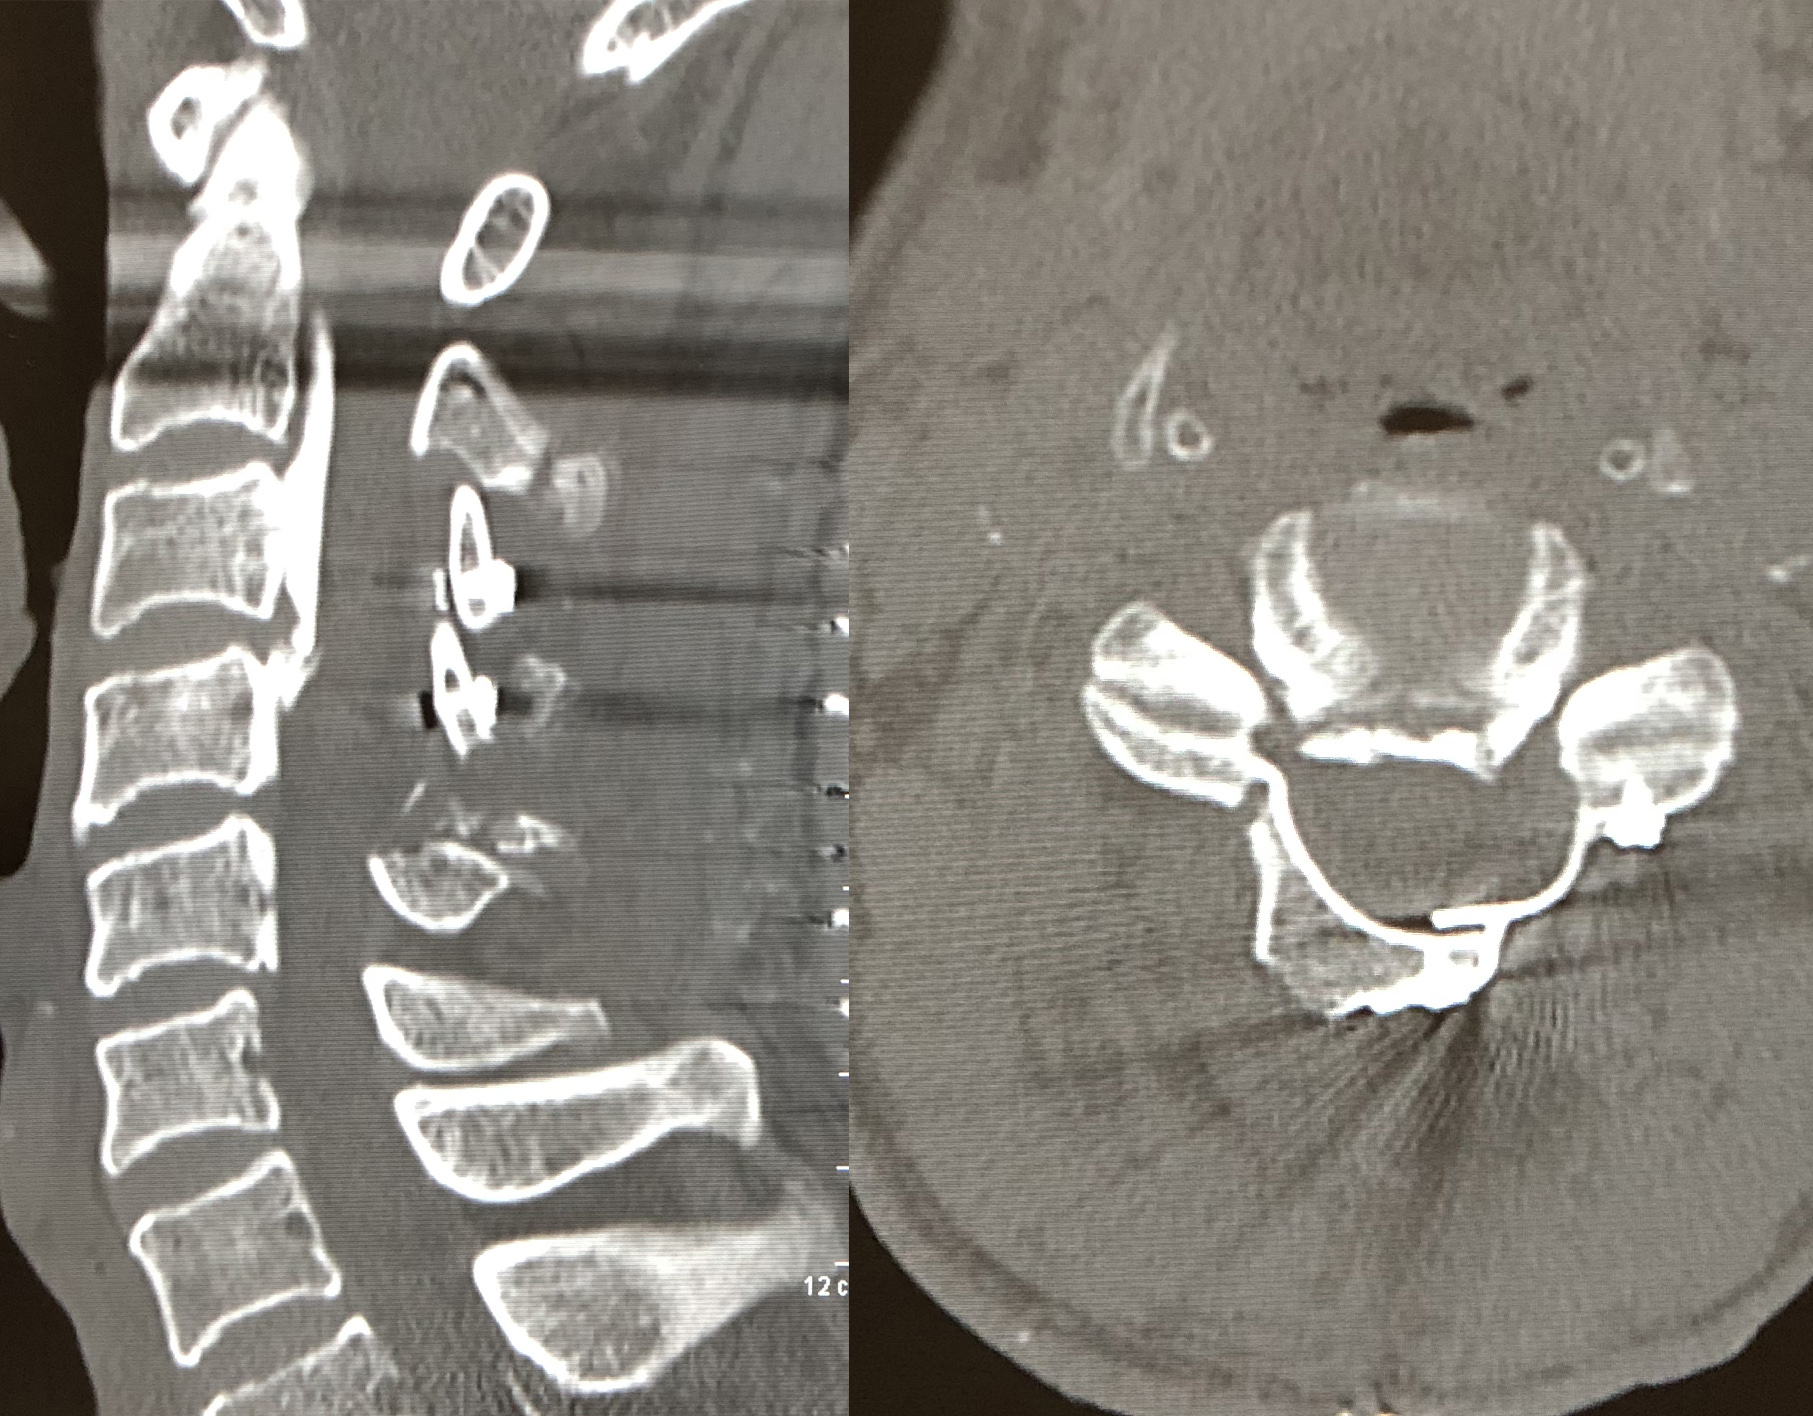

eXtreme Lateral Interbody Fusion(XLIF)は、主に左脇腹からの小皮切で腰椎に側方からアプローチし、脊椎前方に十分な骨移植を行ない脊椎の矯正固定を行なう手術方法です。脊柱管内には一切触れずにす椎間板の高さを増大させてすべりを矯正し、間接的な神経の除圧が可能です。

| 術前 | 術後 | |

| X線 |

| MRI |